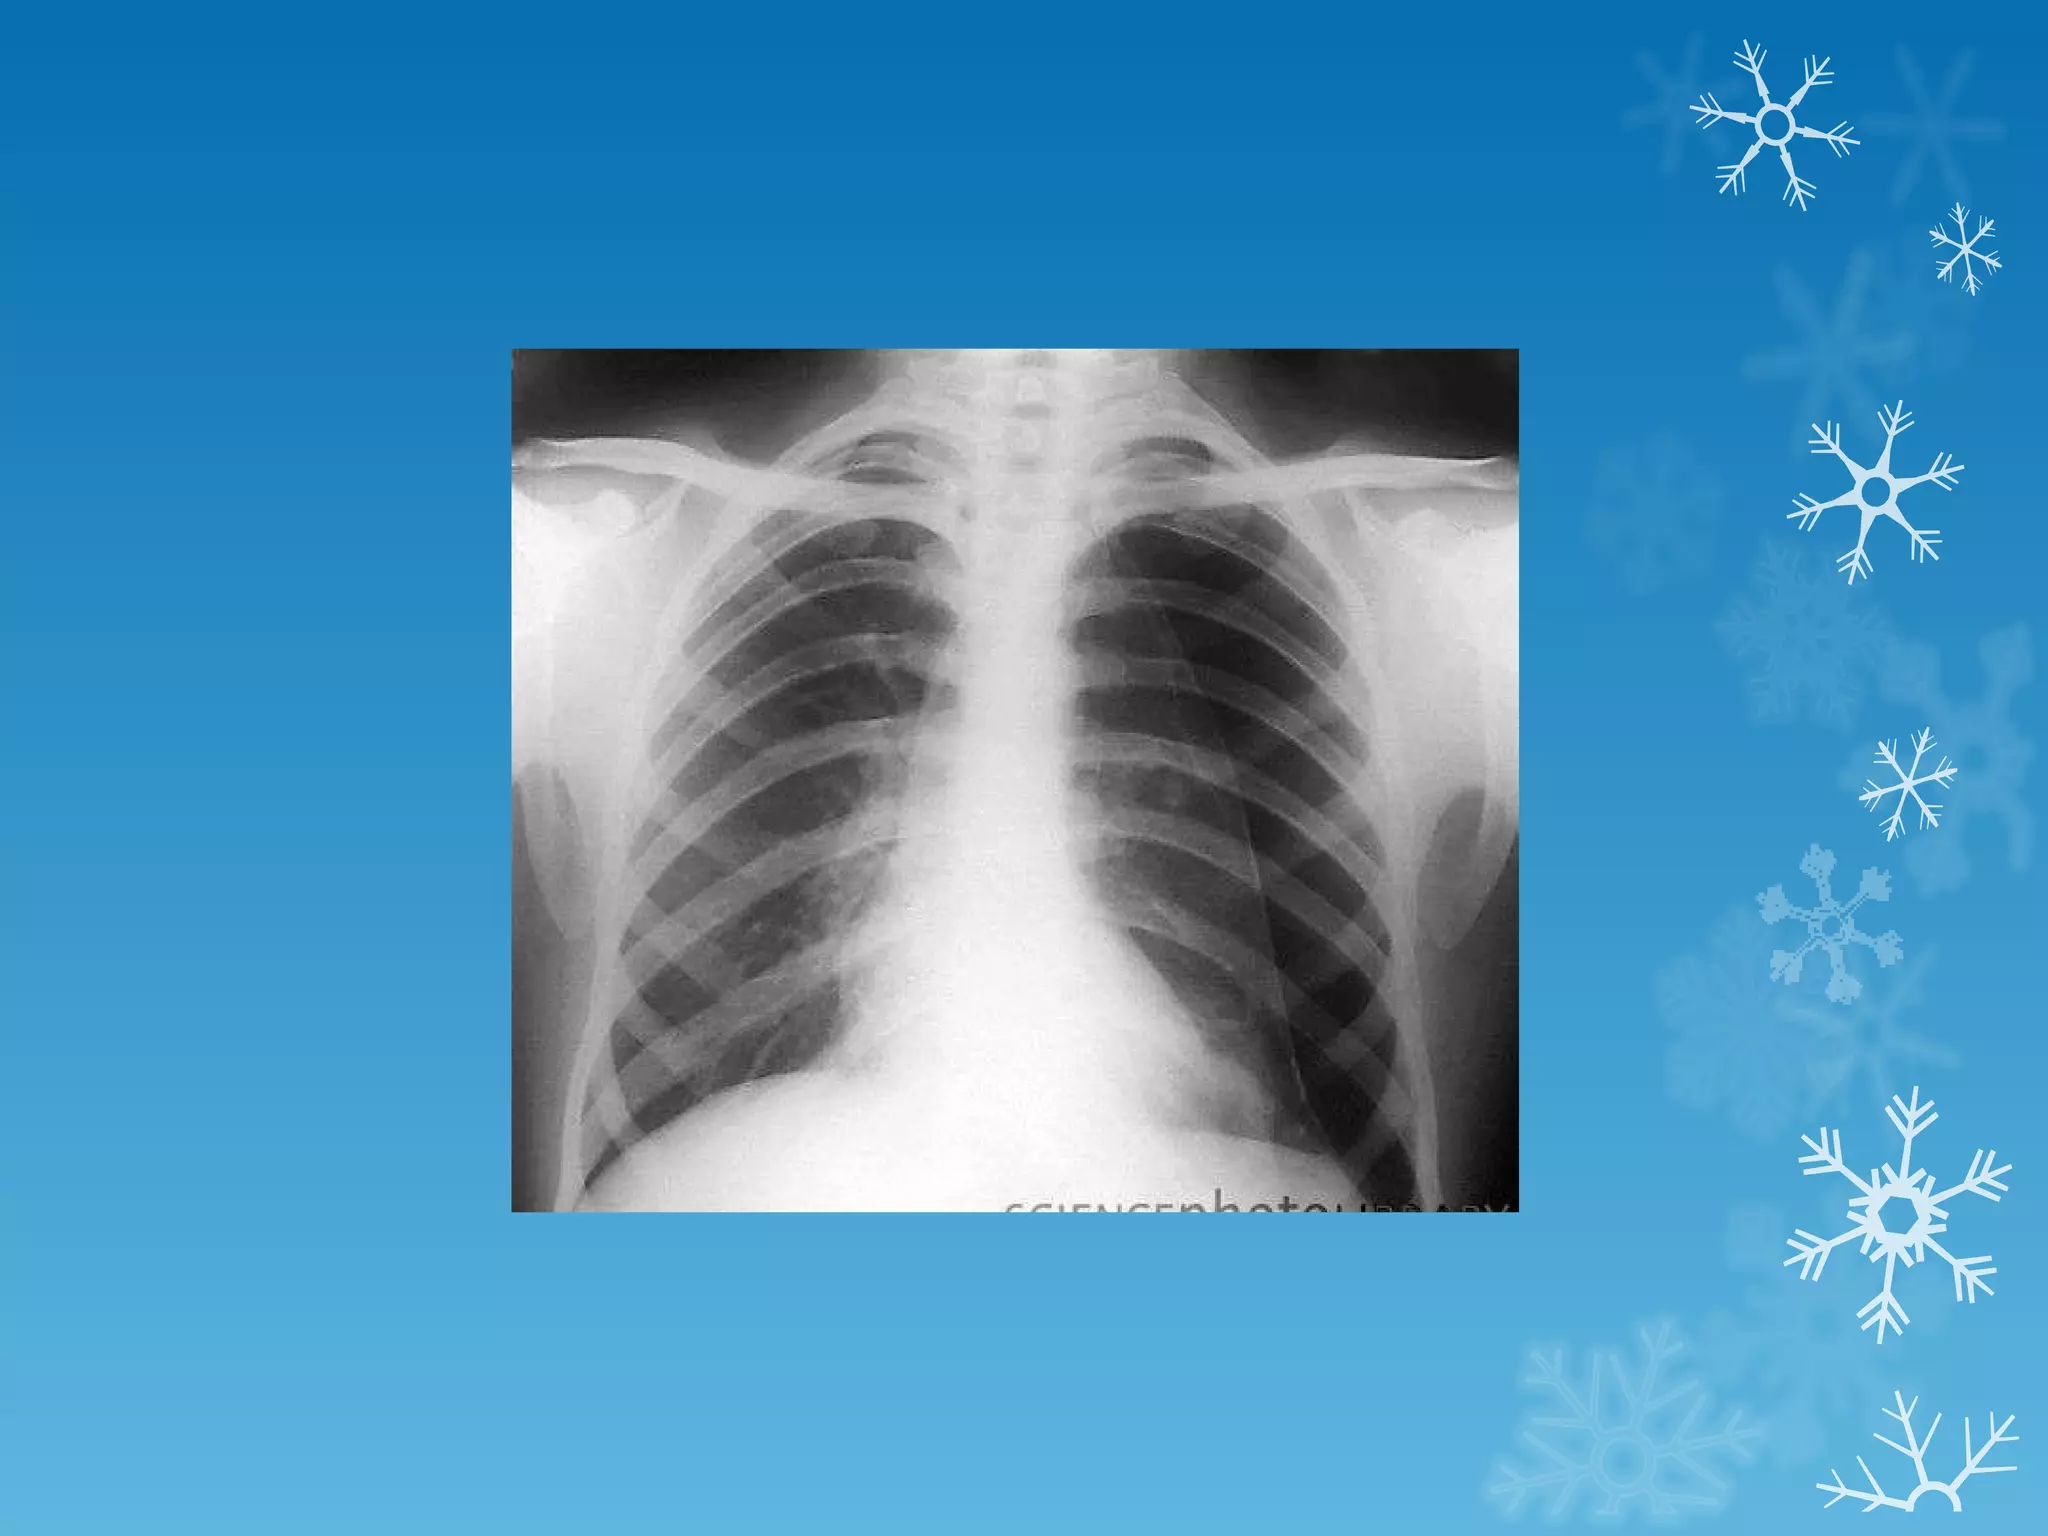

This document discusses chest x-ray interpretation and provides guidance on evaluating x-rays. It explains that tissue density determines how an x-ray beam penetrates, with denser tissues appearing whiter and less dense tissues appearing blacker. It also outlines different chest x-ray views and factors to consider like patient orientation, age, gender, and rotation. Abnormalities are described as appearing too white, too black, too large, or in the wrong place. The document stresses a systematic approach of identifying, localizing, describing lesions, and providing differential diagnoses.